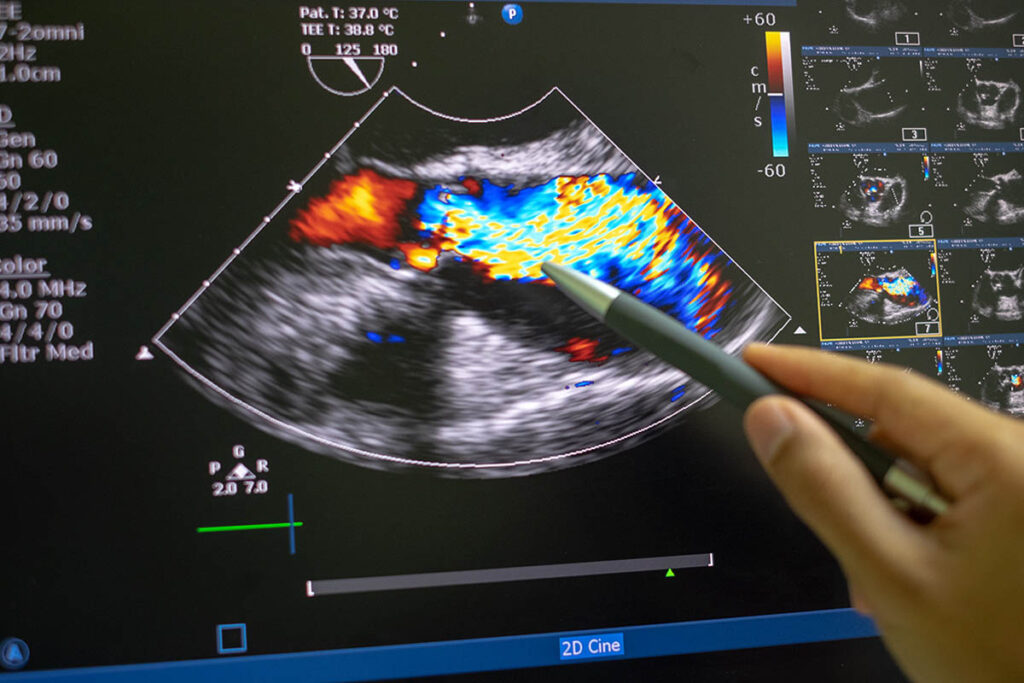

Diagnostic Cardiac Sonography, also known as Echocardiography, uses high-frequency sound waves on patients to aid in cardiac diagnoses. As part of the patient care team, diagnostic cardiac sonographers assess patients and provide information to cardiologists for diagnoses and patient health monitoring.

Discover anatomy, physiology and diseases of the human heart while using the basics of ultrasound physics to operate a state-of-the-art ultrasound system.

Develop scanning skills to safely complete cardiac exams in preparation for assessing real patients. Broaden understanding of heart pathologies.